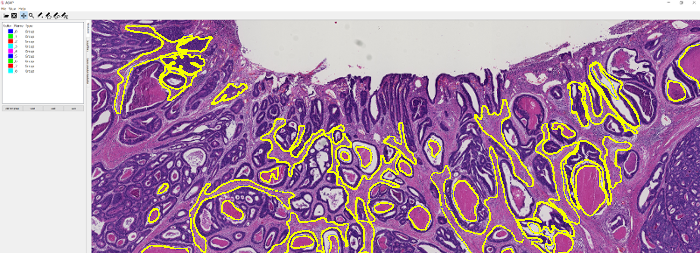

A set of 74 histological slides from 74 patients was prepared from surgically excised rectal carcinomas in patients who had not received neoadjuvant chemotherapy and/or radiotherapy. Slide preparation involved standard fixation of 2m tissue sections and H&E staining. Whole-slide scanning was performed at 200X magnification (pixel resolution = 0.455 m) using a Hamamatsu NanoZoomer 2.0-HT C9600-13 scanner (Herrsching, Germany), which produce 74 gigapixel whole-slide images. Manual annotations of 9 tissue classes were made by an expert using the open source software ASAP555github.com/GeertLitjens/ASAP developed in-house, which included: (i) tumor, (ii) stroma, (iii) necrosis, (iv) muscle, (v) healthy epithelium, (vi) fatty tissue, (vii) lymphocytes, (viii) mucus and (ix) blood cells (see Figure 2). All annotations were successively thoroughly checked by a pathologist and corrections were made when necessary. In the rest of the paper, we refer to this dataset as rectal cancer (RC) data.

2.3 Stain normalization

Stain normalization (SN) involves transforming an image into another image , through the operation , where is a set of parameters extracted from a predefined template image and is the mapping function that matches the visual appearance of a given image to the template image. The parameters are generally defined to capture color information of the main stain components in the image (e.g. H and E). As a result, stain-normalized images will have a distribution of colors that resemble the ones of the template. In Figure 1, images from CRCt and their stain-normalized version based on the WSI template of Figure 2 are depicted.